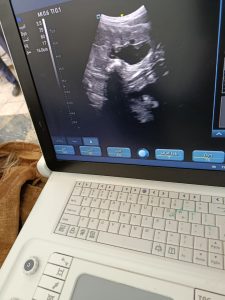

15 ديسمبر,2025وردت إلى المستشفى البيطري التعليمي في المثنى اليوم حالة ماعز تعاني من عسر ولادة بسبب فشل توسع عنق الرحم وكذلك تدلي جزء من المهبل للخارج .. تم الكشف على الحالة باستخدام جهاز السونار. وكانت نتيجة الفحص وجود توأم حي وتقرر على إثرها إجراء عملية قيصرية عاجلة لإنقاذ حياة الأجنة والام … تم إجراء الفحص والعملية بمشاركة أساتذة فرع الجراحة والتوليد وكادر العيادة الخارجية للمستشفى البيطري .. تكللت العملية بالنجاح بولادة توأم ثلاثي جميعهم بصحة جيدة .. تم إعطاء العلاجات اللازمة ما بعد العملية إضافة للتعليمات والتوصيات للمربي للاهتمام بالحالة حتى الشفاء التام.